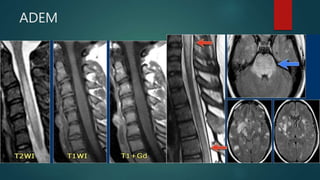

ADEM